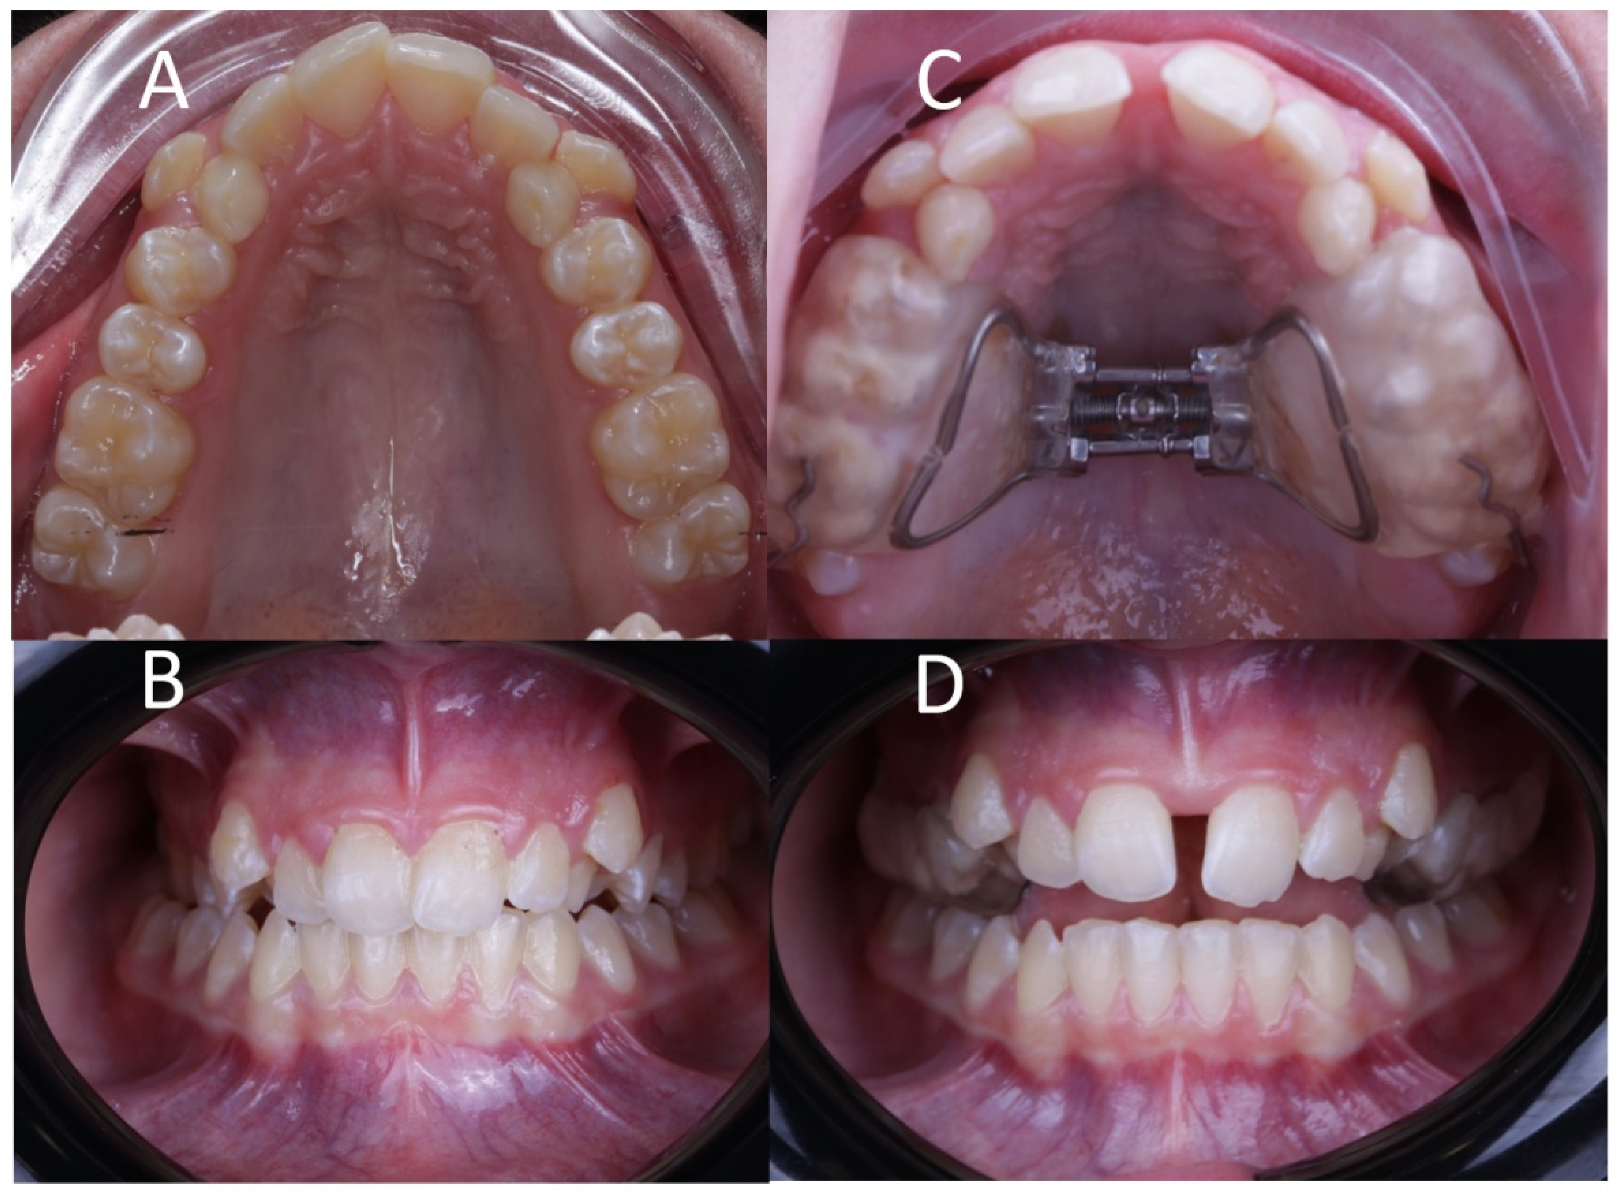

Ten patients (4 male and 6 female) were submitted to palatine suture expansion by RME procedures through McNamara appliance, which is a tooth-supported orthodontic appliance that consists of two acrylic parts attached in the posterior tooth and connected by an expansion screw in the midpalatal region (Figure 1). The inclusion criteria were patients between 9–17 years of age and in good health, who presented signs and symptoms of maxillary skeletal transverse deficiency and A or B stage midpalatal suture maturation according to Angilieri’s classification [24]. Patients who were not within the selected age range, presented a different bone maturation stage (C, D or E), presented systemic conditions, craniofacial syndromes, malformations or had a different diagnosis or treatment plan were excluded. Afterwards, the rapid maxillary expansion procedure through McNamara was made by taking oral impressions with two-phase silicone (Aquasil, Dentsply, Erlangen, Germany). The expansion device was 13 mm long with 1.5 mm thick arms and 0.8 mm full turn (Leone, Florence, Italy) and glass-ionomer cement was used to adhere on the upper molars and premolars. The expansion protocol (Figure 1) was 1/4 turn per day for 15 days (0.4 mm per day), which was the active period of disjunction [26]. The appliance was subsequently kept for up to 9 months of passive retention to avoid relapses.

Figure 1.

(A) Preoperative occlusal and (B) frontal view, and (C) postoperative occlusal and (D) frontal view after RME treatment with McNamara appliance.